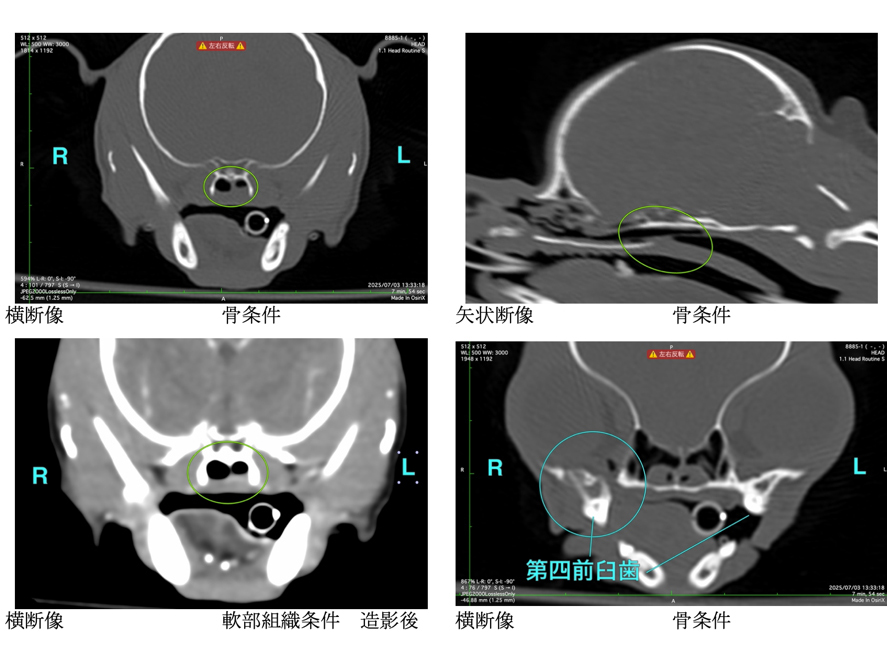

左・下:CT検査にて腫瘍性疾患の否定

数日前に散歩後より急性の鼻炎症状および鼻出血が認められ、鼻腔内異物の存在を強く疑いました。 精査のためにレントゲン検査およびCT検査を実施し、鼻腔内異物および歯根膿瘍の疑いが示されました。 その後、鼻腔内視鏡を用いて異物の摘出および関連する抜歯を実施しました。

CT検査を実施し腫瘍性疾患を否定

当院受診の3日前より、黄色い液体を5?6回連続で嘔吐し、その後より鼻出血および両側鼻腔の通気性低下が認められたとのことで、まず他院を受診されました。 その際に実施されたレントゲン検査では明らかな異常は認められなかったとのことです。 当院にて再度胸部および頭部のレントゲン検査を実施したところ、呼気時における咽喉頭部の一過性の拡張所見が認められましたが、骨の破壊などの明らかな構造的異常は確認されませんでした。 症状の急性発症であること、ならびに鼻閉および鼻出血を伴うことから、鼻腔・鼻咽頭内の異物の存在を強く疑い、同日にCT検査および内視鏡検査を実施しました。 検査の結果、鼻腔から鼻咽頭内にかけて毛玉と思われる異物を認めたため摘出を行ったところ、呼吸状態や全身状態は速やかに改善し、当日中に退院となりました。 その後の経過も良好で、現在までに1年が経過していますが、症状の再発は認められていません。